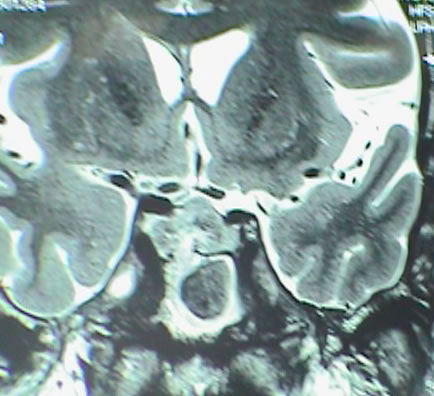

Fig-1: Choline distribution showing a small nidus of possible malignant character befor attacking the lesion.

Fig-5: Choline elevation confirming still persisting active sites intermingled with the hematoma in the right side.